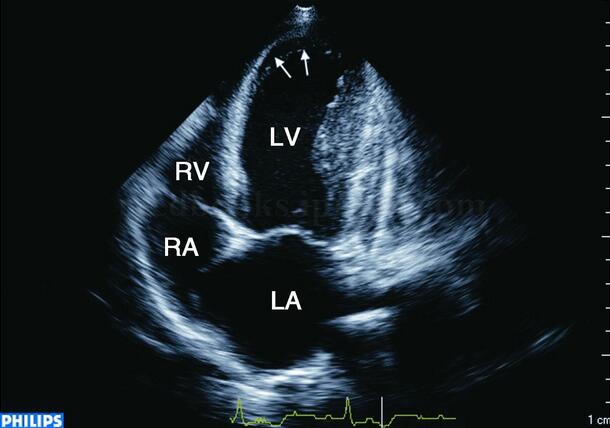

超声图片 如图2‐1‐159。

图2‐1‐159 M型超声显示左室前间壁运动明显减弱,心内膜向心运动幅度为3mm,后壁运动增强,心内膜向心运动幅度为13mm

超声描述 左室前壁、前间壁心肌无明显变薄,向心运动及室壁增厚率明显减低,其余室壁向心运动代偿性增强。左室轻度增大,心尖部扩张,左室EF57%。

超声诊断 左室前壁、前间壁节段性运动减弱,左室泵血功能正常。

临床诊断 冠心病,急性前间壁心肌梗死。高血压3级,极高危险组。

图2‐1‐161 心尖四腔切面显示收缩期心尖部室壁向心运动明显减弱,心尖部心腔向外扩张(箭头)